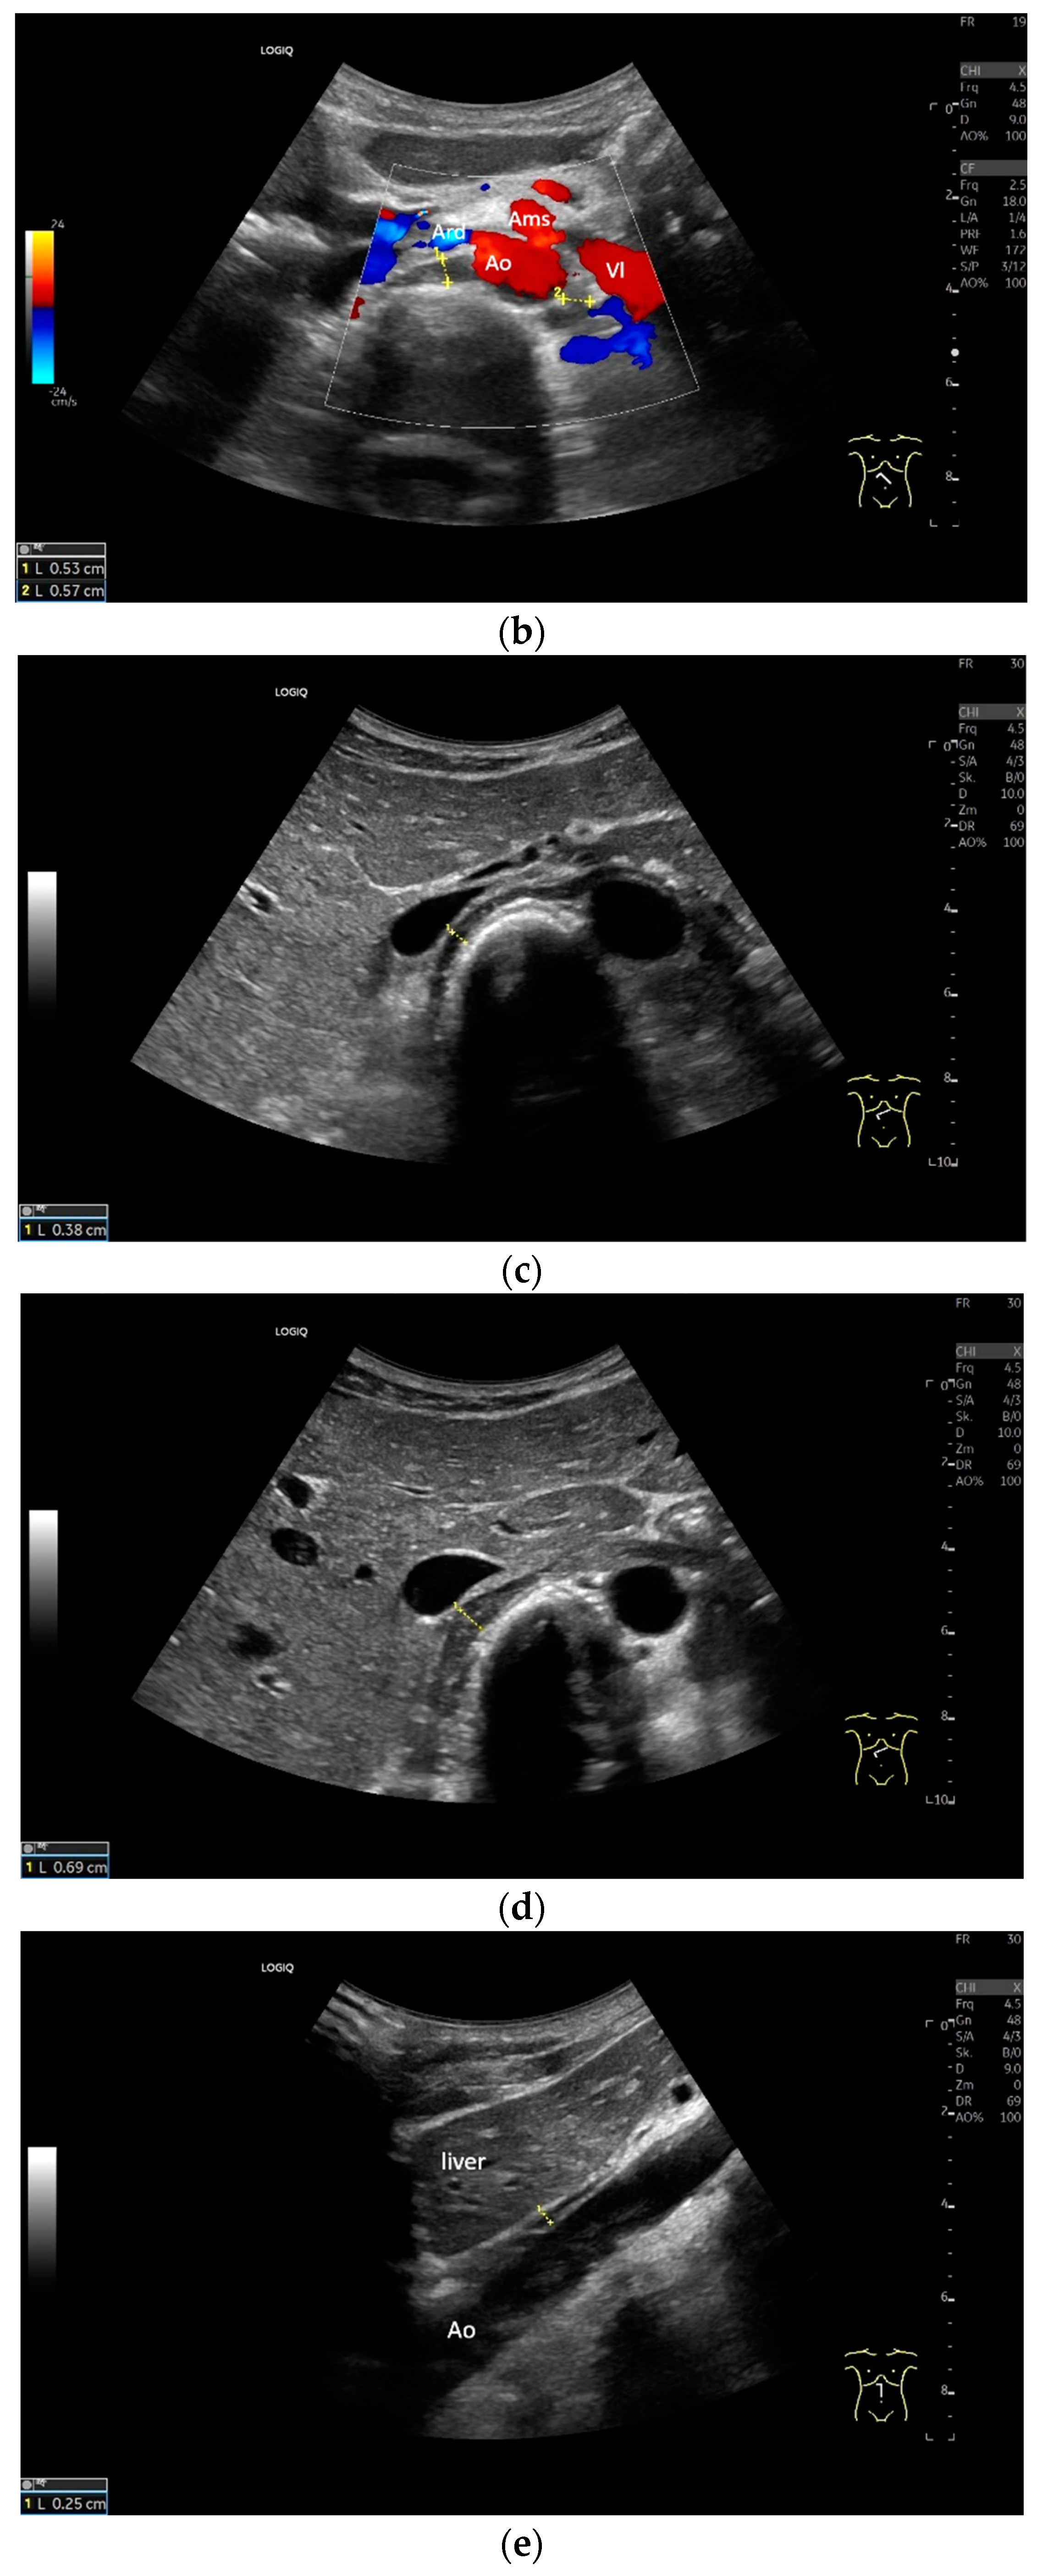

The diaphragm can be assessed in two main transducer positions: lateral in the zone of apposition and subcostal. The zone of apposition is the section where the diaphragm is attached to the inside of the ribs. Measurements are taken in these both positions. In addition, the diaphragm can also be visualized subxiphoidally in the epigastrium in cross section. Depending on the depth of penetration, the examination is performed with an abdominal sector or cardiac transducer (2–5 MHz) or with high-resolution linear transducers. The choice of transducer depends on the depth of the penetration. Some authors choose transducers up to 15 MHz. We prefer a linear transducer up to 9 MHz. The assessment is conducted in B-mode ultrasound (US) and in M-mode US.

Lateral transducer position in the zone of apposition: The transducer is positioned longitudinally and laterally in the area of the mid-axillary line or slightly ventral to it between the anterior and mid-axillary lines, approximately in the 8th or 10th intercostal space. The diaphragmatic reflex is located on the inner side of the ribs below the pulmonary glide with pulmonary reverberations. This localization of origin of the diaphragm from the inner side of the rib cartilage is referred to as the zone of apposition (Figure 3). As this localization is only a few centimeters below the skin surface, high-resolution linear transducer use is highly recommended. In this position, the diameter of the diaphragm is measured during inspiration and expiration [2,3,4,5] (Figure 4). The thickness of the diaphragm varies, with caudal parts being thicker than cranial parts. The measurement of diaphragm thickness is highly variable depending on the intercostal space chosen, with thickness varying by up to 6 mm between the intercostal spaces [6]. It is therefore important to select the same position for comparable measurements and, if necessary, to mark the location for the transducer position [7]. Obesity limits assessment of the diaphragm [2].

Subcostal transducer position: An abdominal sector or cardiac transducer (2–5 MHz) is used in the subcostal window. This position is used to assess diaphragmatic excursion. The transducer is placed between the linea medioclavicularis and linea axillaris anterior. The diaphragmatic excursion can then be visualized and measured in M-mode (Figure 5). The gallbladder and inferior vena cava are important landmarks. It is important to guide the ultrasound probe as perpendicularly as possible. The M-mode axis should meet the diaphragm at an angle of 90%. In this position, diaphragm thickness in inspiration and expiration can also be measured using M-mode, and diaphragm shortening can be calculated. However, in normal adults, the diaphragm can usually only be visualized in this position using abdominal sector transducers and is less accurately delineated than with a linear transducer from the lateral side in the anterior axillary line.

Subxiphoid: The diaphragm can be positioned directly subxiphoidally with a slightly sagittal transducer position on both sides next to the attachment to the sternum. The diaphragm limb can be demarcated to the right in the epigastrium in cross section between the aorta and the inferior vena cava. However, this is primarily of differential diagnostic importance, e.g., in relation to lymphomas, not for the actual assessment of the diaphragm (Figure 6).

Regardless of the recommended positions for standardized measurements, the diaphragm can be viewed in other areas. This works quite well on the flank and subcostally in the midclavicular line (Figure 7).